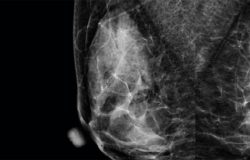

Rose M

Detectores Especializados

Obtenga una calidad de imagen nítida, una adquisición más rápida, una gestión del flujo de trabajo sin esfuerzo y dosis bajas para sus pacientes con los detectores especializados Rose M y el software de adquisición intuitivo RConsole1.